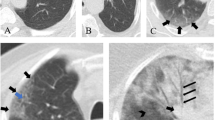

CT images were prospectively interpreted by one of two radiologists with 2 and 5 years of experience, taking into consideration the available clinical information and the result of the nasopharyngeal swab if available at the time of CT interpretation (N = 71). Signs of COVID-19 infection included ground glass opacities in a multifocal peripheral distribution, crazy paving, vascular dilation, subpleural bands and consolidations (Fig. 1) [7, 21,22,23,24,25,26,27,28,29,30]. A semi-quantitative evaluation of parenchymal involvement was also performed. A categorical assessment scheme was used to conclude the study regarding the probability of COVID-19 infection as follows: 1: normal exam, 2: other infection is more likely, 3: indeterminate for COVID-19, moderate probability, 4: highly suggestive of COVID-19, 5: typical findings for COVID. In this paper, scores ≥ 3 were considered positive for COVID-19 [31].